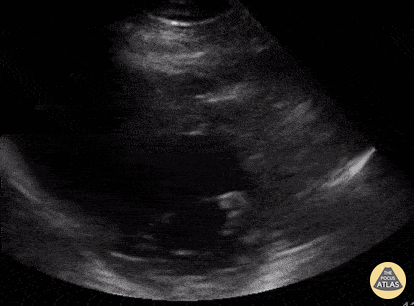

Other Cardiac Pathology - LV thrombus, parasternal short axis

Parasternal short axis view of a 47yo with PMH non-obstructive CAD incidentally found to have mildly reduced LV systolic function and an echogenic mass in LV extending to outflow tract. Determined to be a large LV thrombus of unknown etiology. Andrew Balster, MD Paul Musgrave, MD (OHSU IM POCUS fellow) @POCUSaurusDx